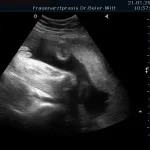

Frühschwangerschaft:

Ultraschall_10